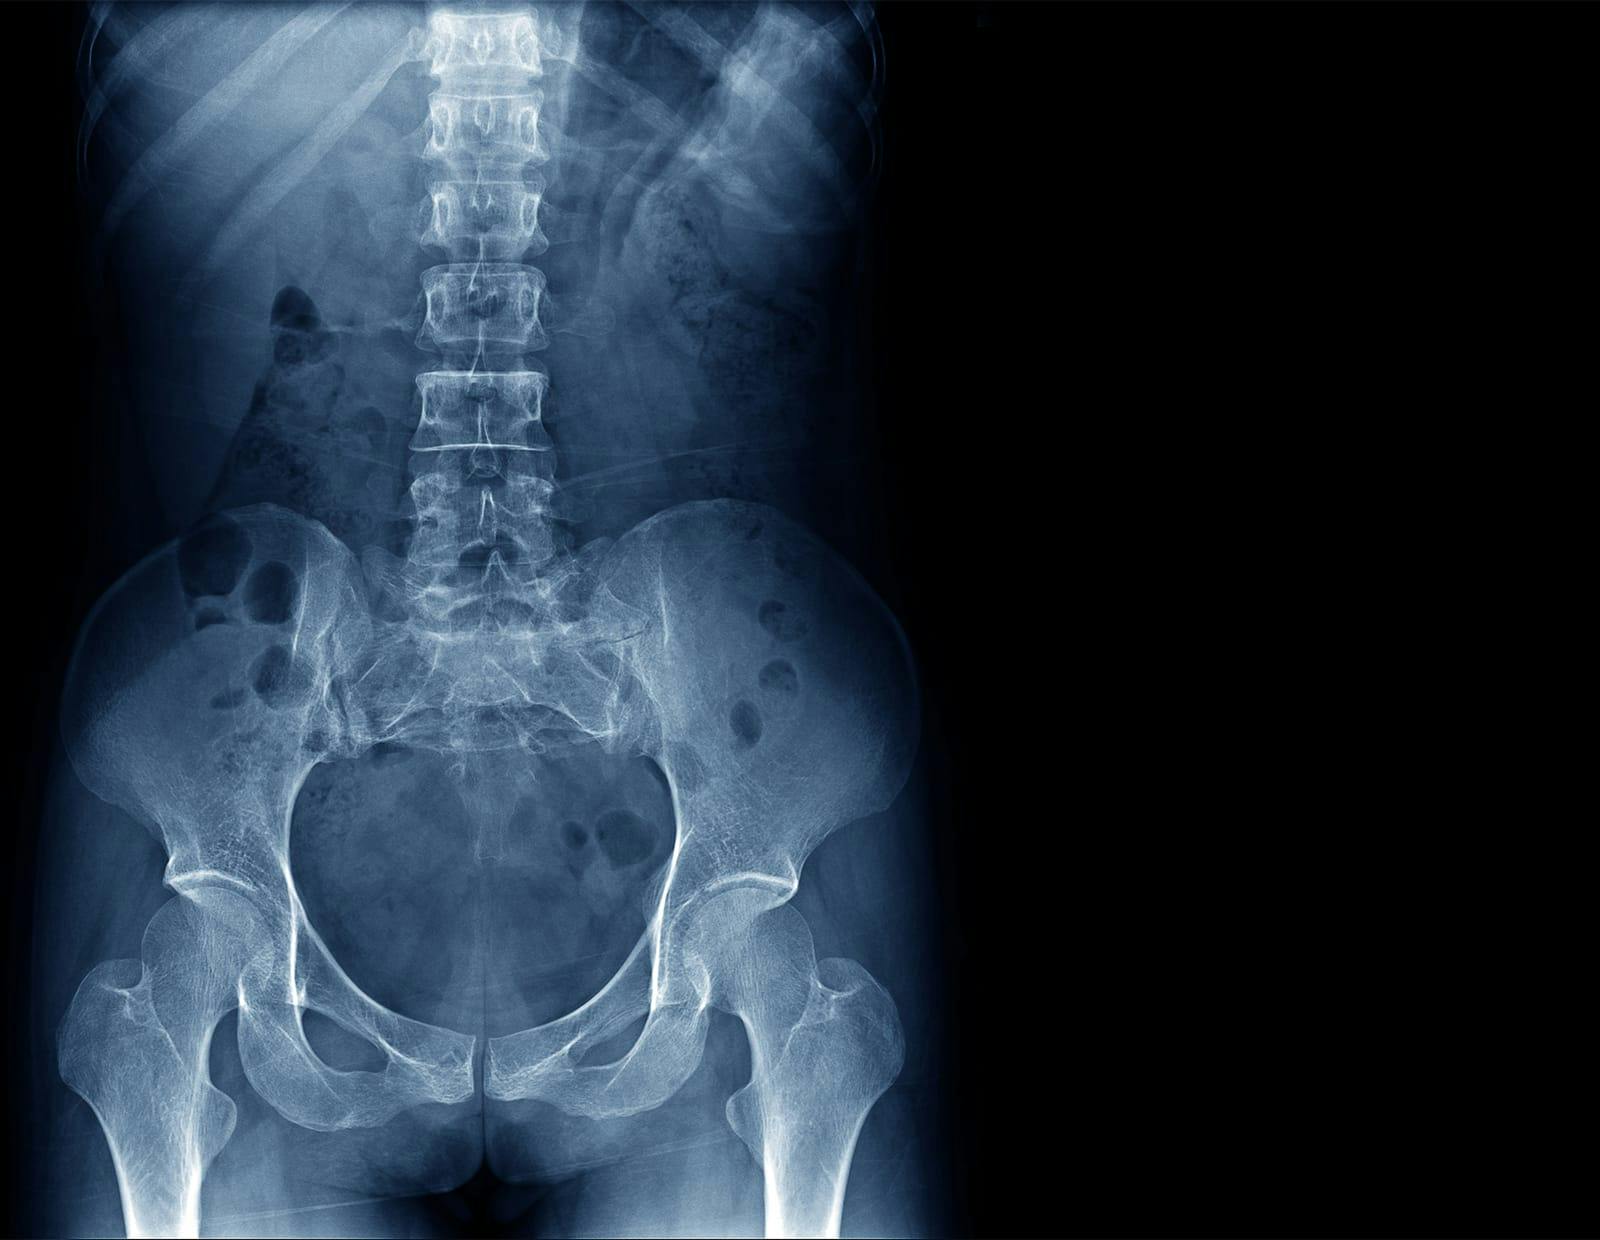

At Gerling Spine Care NJ, we specialize in advanced treatments for sacroiliac (SI) joint dysfunction, including Sacroiliac Joint Fusion Fixation Stabilization. This procedure is designed to alleviate chronic pain in the lower back and buttocks caused by instability or degeneration of the SI joint, a critical connection between the spine and pelvis. Our expert team, led by Dr. Michael Gerling, is dedicated to providing effective, personalized care for patients in New Jersey, using state-of-the-art techniques for faster recovery and improved outcomes.

Sacroiliac Joint Fusion is typically recommended for patients experiencing chronic, debilitating pain due to:

- Sacroiliac Joint Dysfunction: This can result from degeneration, inflammation, or damage to the joint.